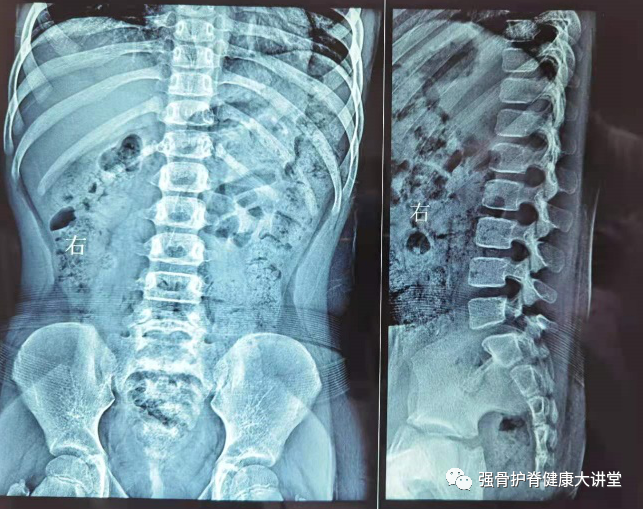

腰椎峡部裂1例

分享典型病例椎弓崩裂患者影像图片

一例腰痛20余年的患者确诊为"腰5椎体滑脱,腰5双侧椎弓峡部-孟繁春

硬化显著,矢状位重组显示腰5椎弓峡部崩裂(长↑)china-radiology审稿